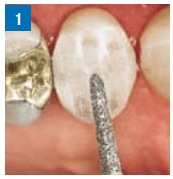

- Ranhuras de orientação oclusal com ponta diamantada cônica 6878K.314.016.

- Ranhuras de orientação vestibular e palatina com o mesmo instrumento.

De acordo com esses sulcos, o preparado na vestibular e palatina é de maneira supragengival.